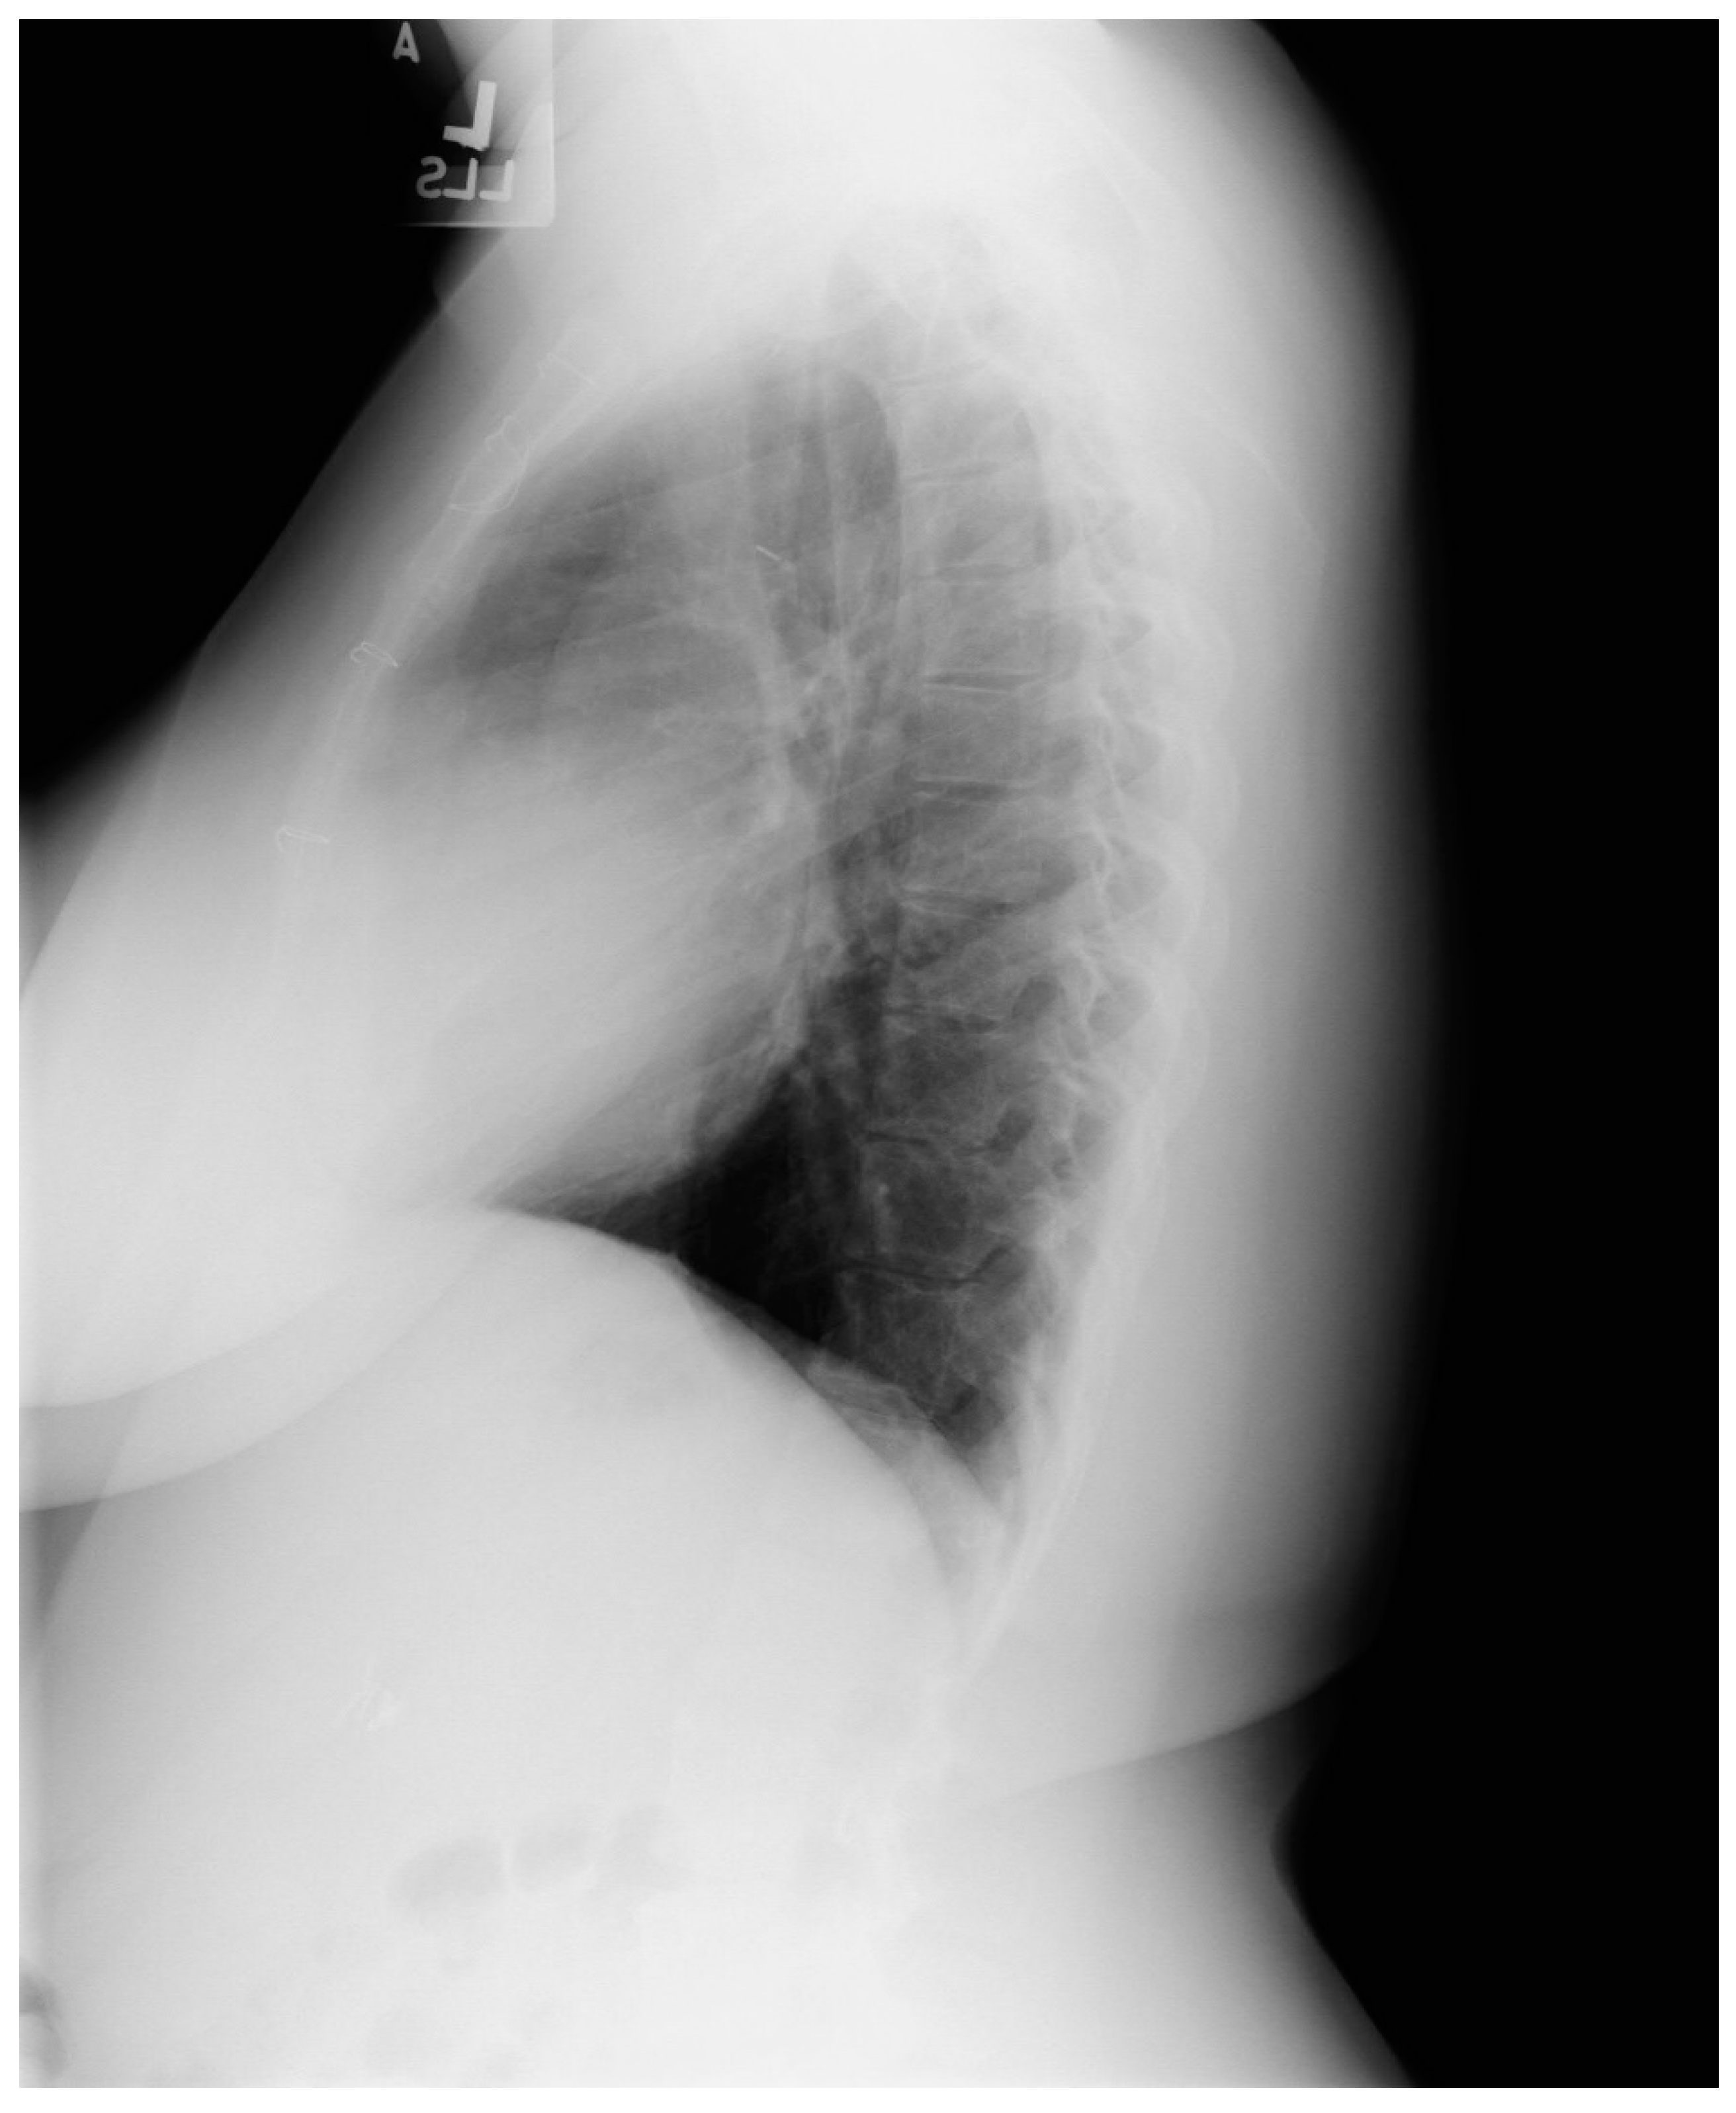

Figure 14.

Lateral chest X-ray in congenitally corrected transposition of the great arteries in adulthood: this is the lateral chest X-ray of the same 41-year-old male in Figure 13. There are sternal wires from the median sternotomy used to repair his atrial septal defect, remote from this presentation. The retrosternal airspace is opacified, suggesting right ventricular enlargement. On examination he had a holosystolic murmur of atrioventricular valve regurgitation. Doppler echocardiography demonstrated severe systemic atrioventricular valve regurgitation (the anatomic tricuspid valve), and moderate dilatation of the systemic ventricle (the anatomic right ventricle) with preserved systolic function. He underwent replacement of the systemic atrioventricular valve with a dual-tilting disc mechanical prosthesis and did well. Optimally, the transition from pediatric congenital heart disease care to adult congenital heart disease care should be a coordinated hand-off [12].